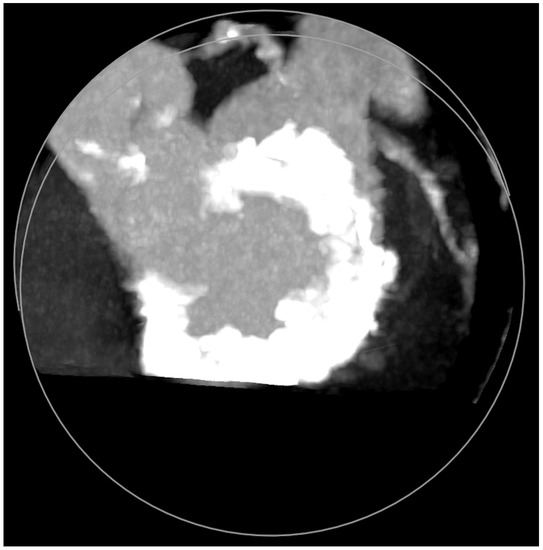

MAC consist of circumferential calcific depositions around the mitral valve, especially in the posterior aspect (Figure 5), but sometimes involve the whole mitral fibrotic annulus. It is considered a chronic degenerative condition, although it may be associated with rheumatic mitral disease. It is important to note that MAC has been clearly associated with a worse prognosis due to coronary artery disease and myocardial ischemia, ventricular arrhythmias, cardiovascular events (including mortality), and mitral and aortic valve dysfunctions [11]. MAC more frequently cause MR than MS [12]. Cardiac imaging tools, which are important before mitral lithotripsy, become critical when planning a ViMAC procedure. Apart from transthoracic echocardiography, TEE, and fluoroscopy, cardiac computed tomography (CT) with contrast has emerged as the cornerstone imaging modality since it allows the quantification of the density, severity, and extension of MAC and its relationship to other cardiac structures [13].

Figure 5.

Mitral annular calcifications (MAC), which allow grading of the valvular calcium burden and extension.